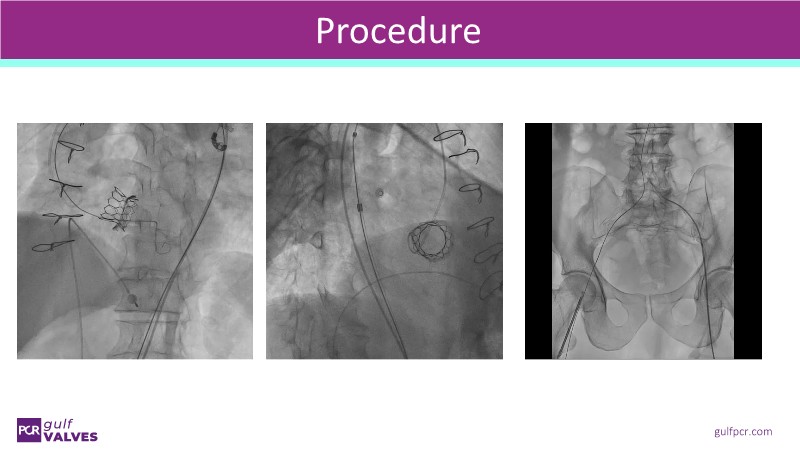

Join this comprehensive session to explore the Myval transcatheter heart valve series, featuring the latest clinical updates from two large randomized controlled trials—Landmark and Compare TAVI. Learn from real-world experiences, including recorded cases, and understand how these innovations translate to complex patient demographics in daily TAVI practice.